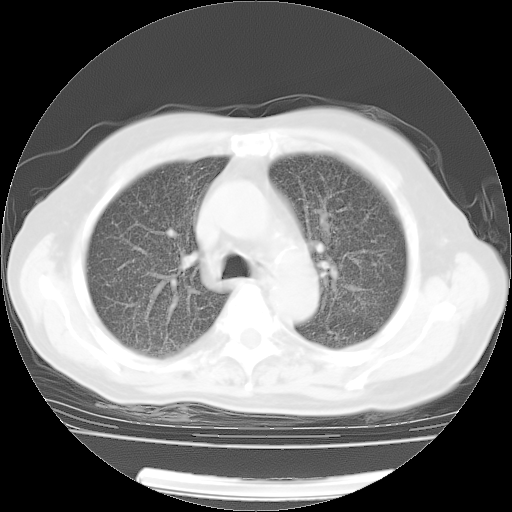

肺部CT平扫未见异常。